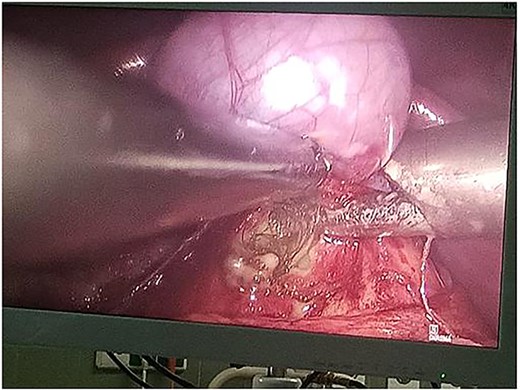

Following multidisciplinary consultation, the lesion was diagnosed as an E. granulosus hydatid cyst. Laparoscopic resection was planned (Fig. 2). Intraoperatively, surgeons suspected the cyst might represent a teratoma. Resection was performed under vascular clamping, with the cutting plane passing through healthy tissue, ensuring complete removal of the cyst wall (Fig. 3). The surgery was uneventful.

Resected specimen of the hepatic cystic mass, removed laparoscopically under vascular clamping. The excision was performed through healthy liver parenchyma, ensuring complete removal of the cyst wall. The gross appearance, featuring heterogeneous soft tissue components and hair-like structures, initially raised suspicion of a hepatic teratoma among the surgical team.

Complete surgical excision remains the definitive treatment [10]. The cyst was removed laparoscopically, and upon aspiration, a large amount of pus was released. Hair and teeth were found upon opening the cyst wall. The procedure was converted to open laparotomy to ensure full resection.